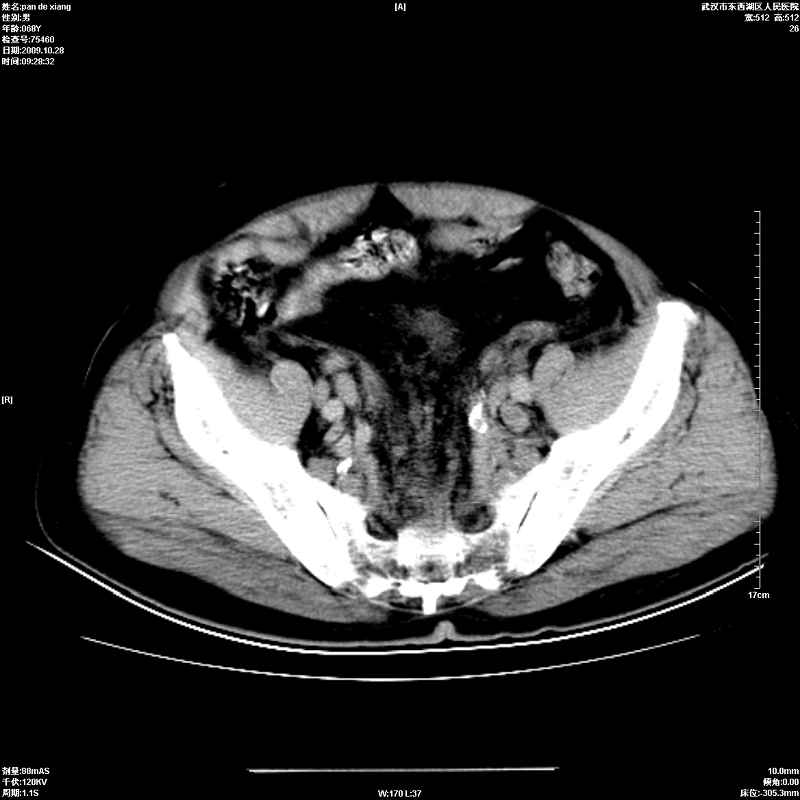

以下是引用杀毒软件在2009-10-28 20:41:00的发言:[br]结合临床考虑---白血病双肾改变或淋巴瘤。

以下是引用zxl51642在2009-10-29 9:59:00的发言:[br]结合临床“单克隆免疫球蛋白血症”,考虑双肾为继发损害并肾功能不全(尿中大量igg及少量iga、igm等大分子免疫球蛋白滤出所致继发损害),椎前软组织肿块为髓外造血。与浆细胞瘤有区别,平扫时有战友说的很清楚。